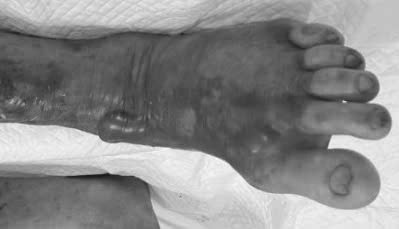

Bệnh nhân T. (59 tuổi) nhập viện trong tình trạng hoại tử lan nhanh ở vùng cẳng chân trái, kèm theo phỏng nước, sưng đau, sốt và tổn thương đa cơ quan (gan, thận). Chỉ trong 1-2 ngày, các vùng da bị nhiễm trùng chuyển màu tím đen, lan đến cả đùi và bẹn.

Hình ảnh tổn thương của người bệnh T. do nhiễm vi khuẩn ăn thịt người. Ảnh: BVCC.

Khi xâm nhập vào cơ thể, vi khuẩn Vibrio vulnificus tấn công mô mềm và lan rộng chỉ trong 12-48 giờ. Vùng da nhiễm khuẩn sưng đỏ, đau nhức, sau đó xuất hiện bóng nước tím đen hoặc hoại tử. Nếu không được điều trị kịp thời, tình trạng có thể tiến triển thành viêm cân mạc hoại tử - dạng "nhiễm khuẩn ăn thịt người" nguy hiểm, dẫn đến sốc nhiễm khuẩn, suy đa tạng và không qua khỏi.